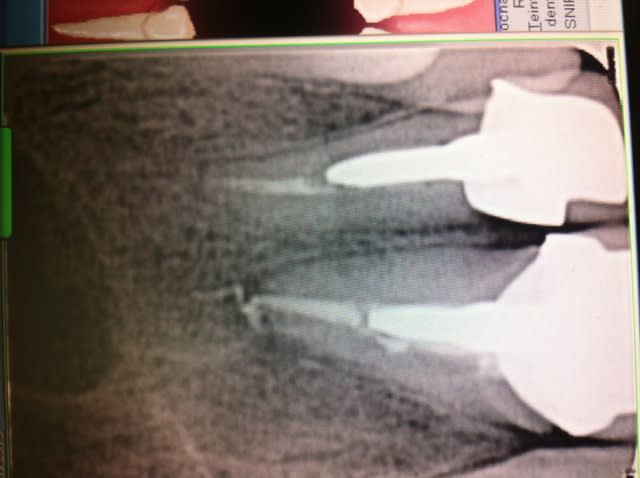

Ras à la rétro sauf un petit dépassement sur 21. Gencive tuméfiée, violacée en vestibulaire de 21-22. La 21 a déjà eu un Rte il y a 4 ans.

Rien au sondage, mais en regardant de plus prés la rétro, je suspecte un trait de fracture en distal de 22...

Mis sous Antibio, plus de signe clinique. Prescription de cone Beam et surprise, belle image...

La rog sera obligatoire, j'ai même un peu peur malgré tout de la finesse du mur vestibulaire.

Idem pour la 22 qui est surement fracturée

Que penses tu de la taille de la lésion?

Elle est quand même volumineuse. Tu penses qu'en greffe d'apposition pourrait être envisageable?